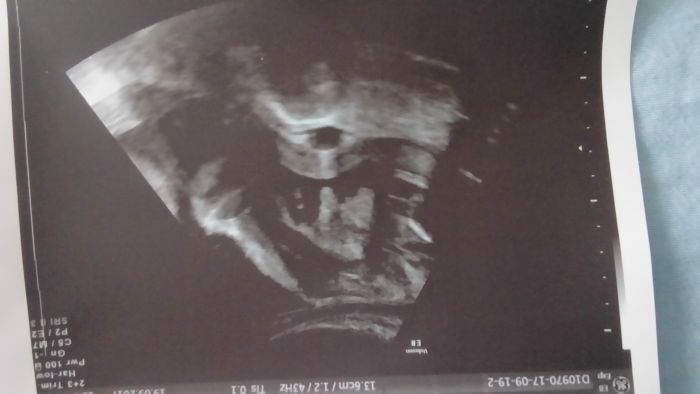

kontrola super dopadla mile mě to překvapilo vše je OK sice jsem tenhle měsíc já fyzicky nic nepřibrala ale Vikoušek krásně roste je ukázkovej žepry má už 1100-1200g a je už otočený hlavičkou dole

Jinak přikládám fotku to v prostředku je pindik s pytlikem :D